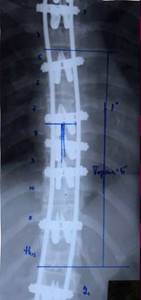

| Динамический корректор. Результат на 2-е сутки после операции |

| Результат коррекции сколиотической деформации эндокорректором с деротационными скобами |

Результат оперативного лечения. Коррекция 100% |